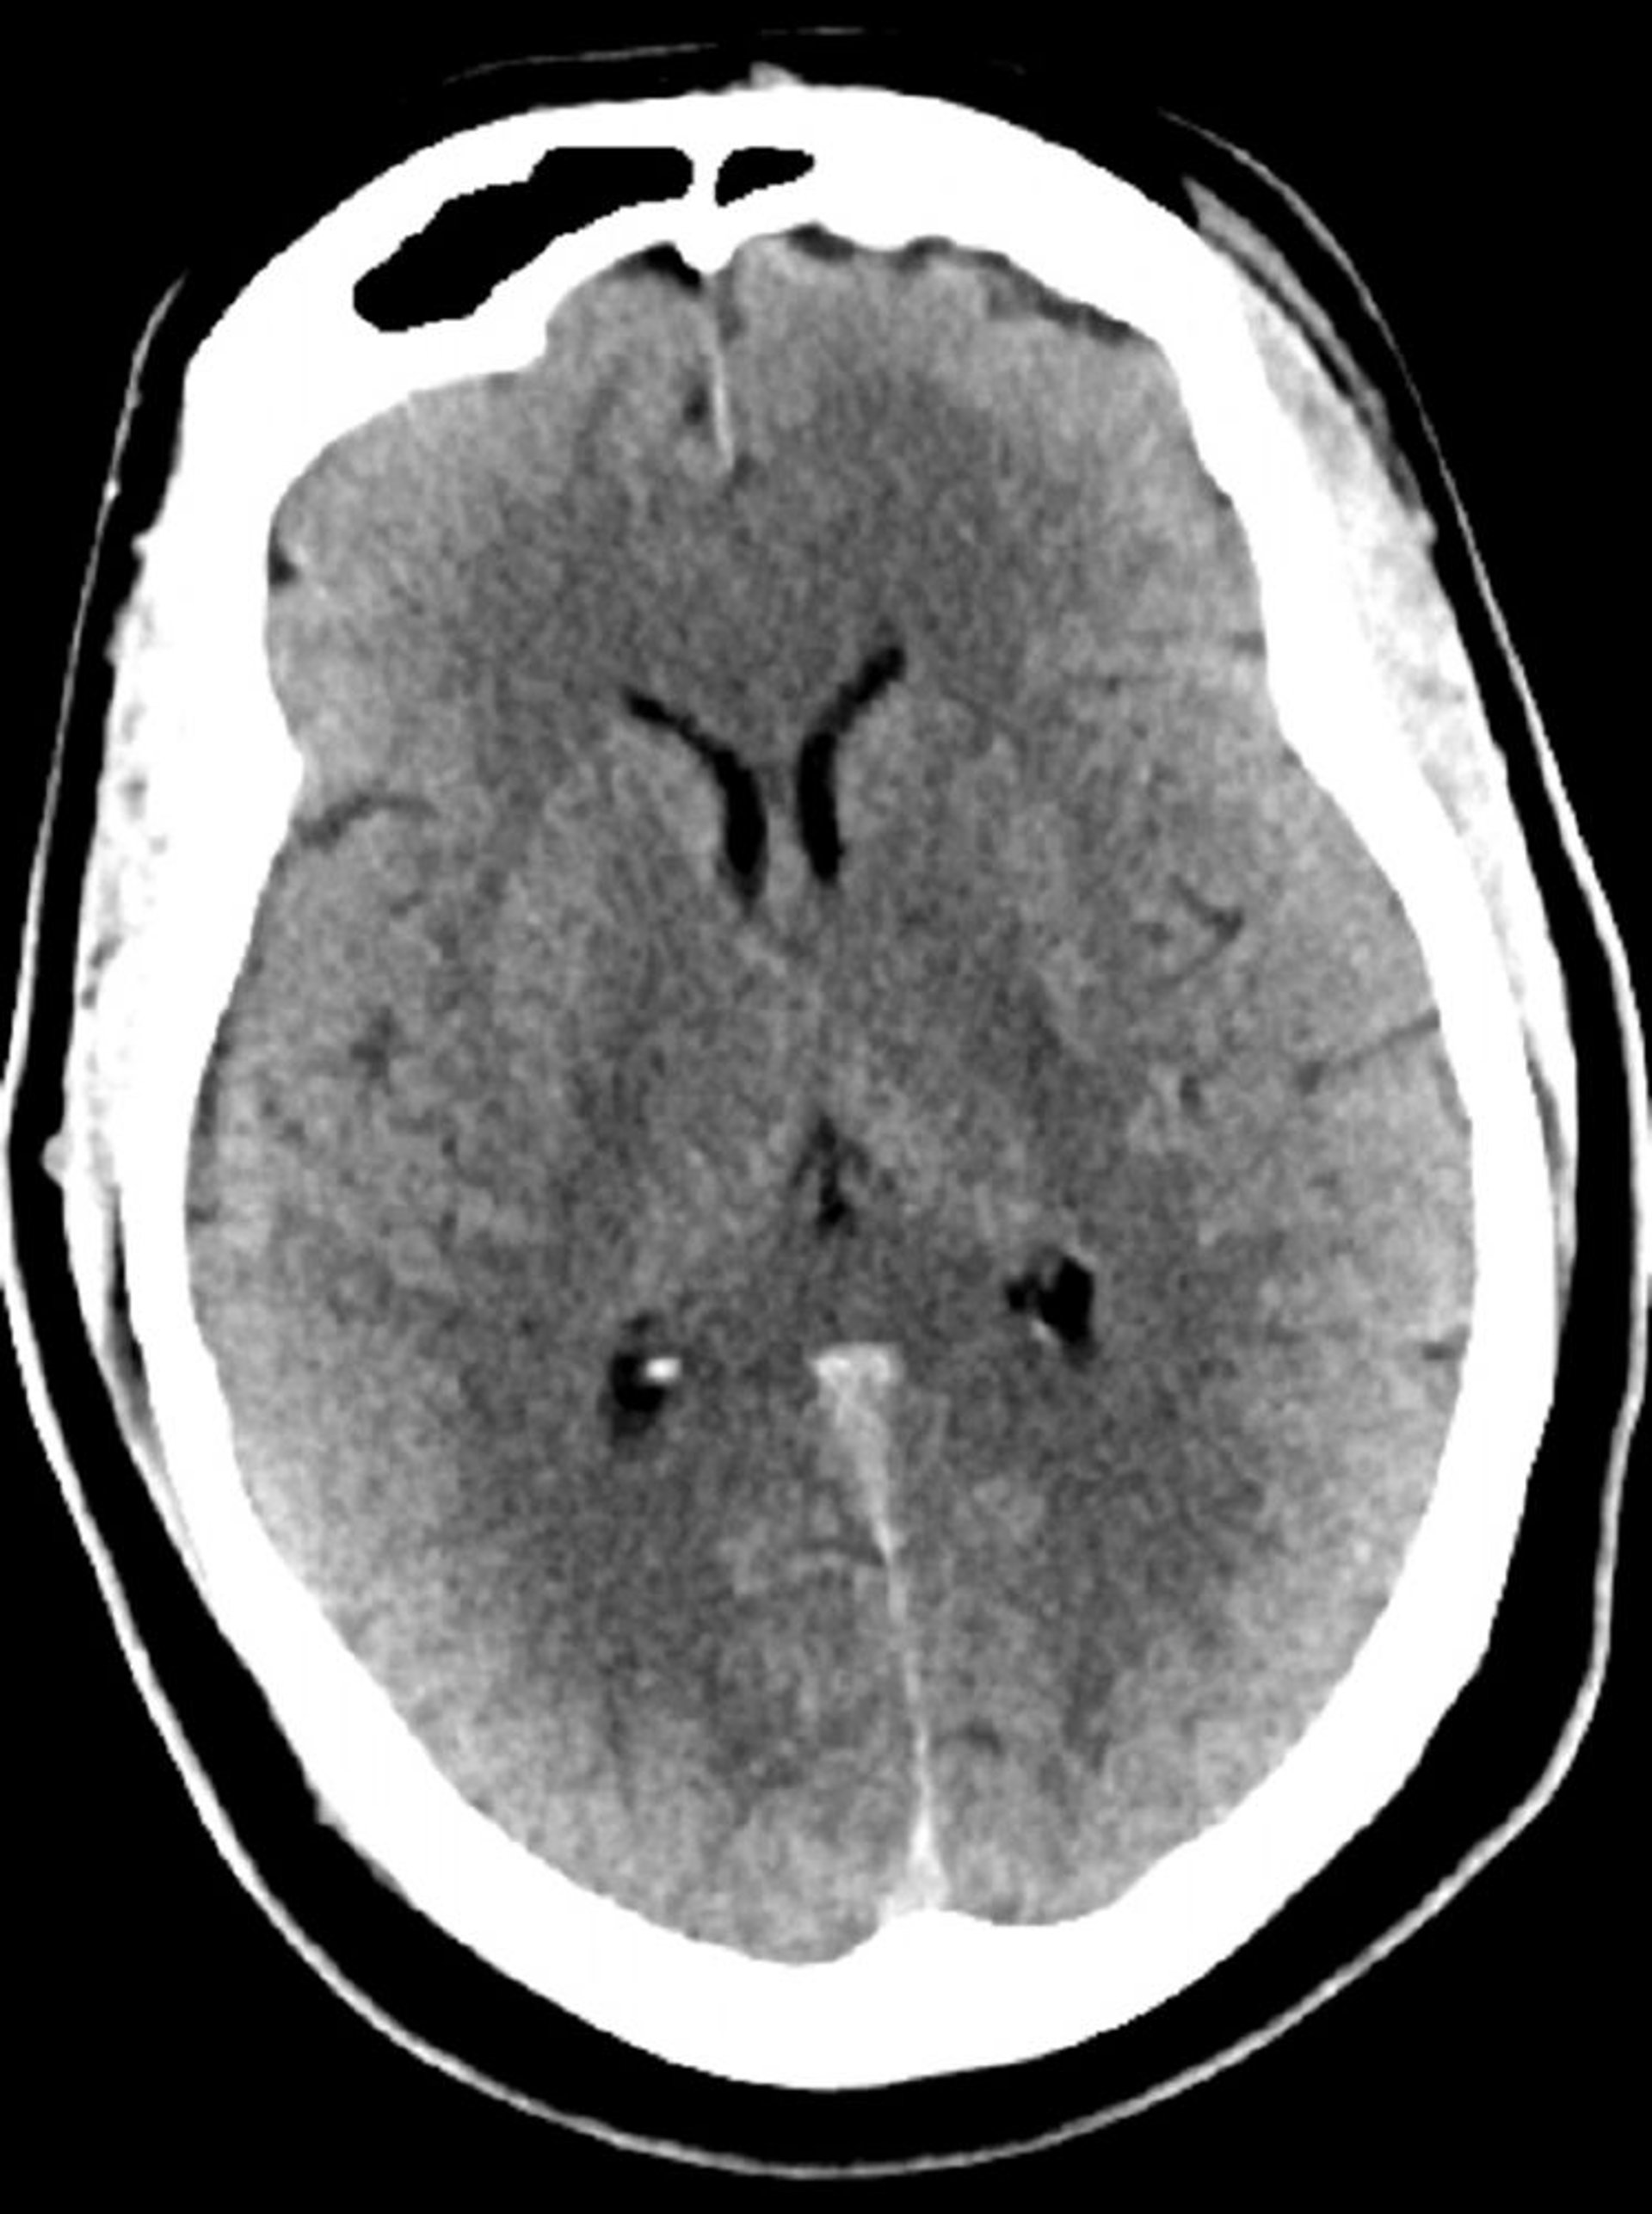

Tomodensitométrie normale de la tête (adulte, 30 ans) – Diapositive 5

Cette image est une TDM normale de la tête d'un jeune adulte âgé de 30 ans. Il n'y a pas de liquide intra- ou extra-axial ou d'hémorragie. La différenciation gris-blanc est préservée. La taille du ventricule et la forme des sillons semblent normales.